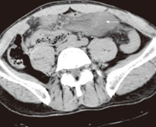

CT κοιλίας. Πρόπτωση παχέος εντέρου διά του κατώτερου οσφυϊκού τριγώνου (Ευγενική παραχώρηση Dr. V. Penopoulos)